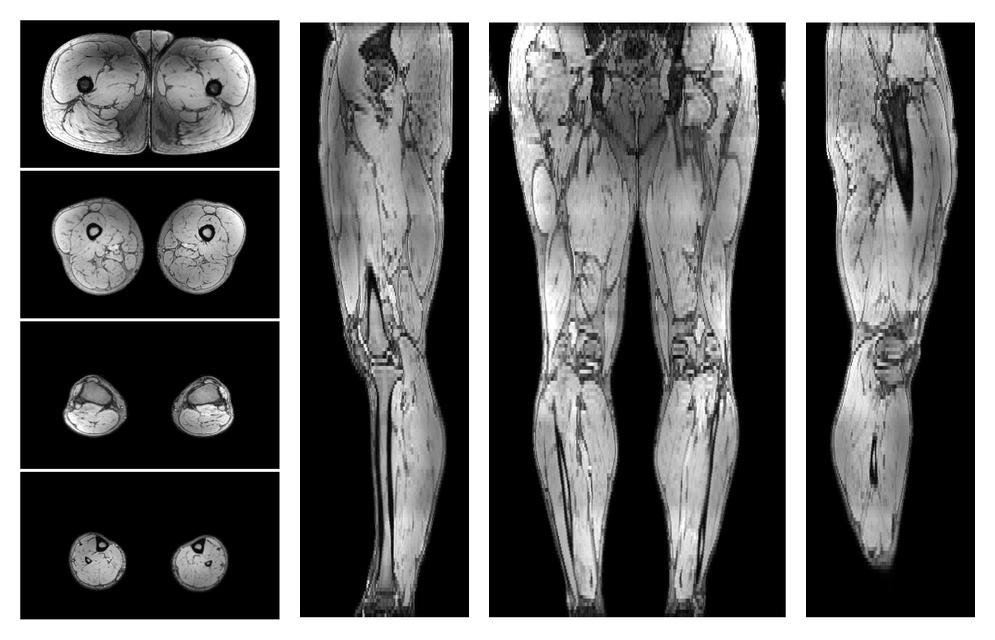

• Water only signal

The water part of the acquired multi-echo spin echo data.